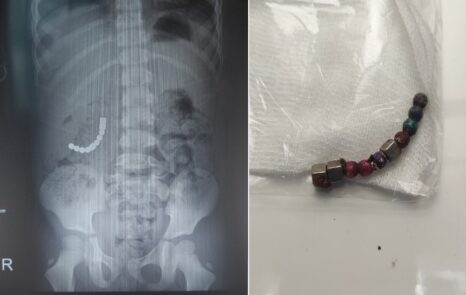

Bệnh nhi 5 tuổi vô tình nuốt phải các viên bi nam châm, dẫn đến tình trạng thủng ruột non, tá tràng.

Các bác sĩ tại Bệnh viện Sản Nhi tỉnh Bắc Ninh vừa phẫu thuật lấy dị vật có từ tính (nam châm) trong bụng bệnh nhi Đ.M.Đ. (5 tuổi, trú tại đường Đại Phúc, TP Bắc Ninh). Đây được đánh giá là ca bệnh hiếm gặp, không phẫu thuật kịp thời có thể gây hoại tử và nhiều hậu quả nghiêm trọng.

Dị vật nam châm đã được lấy ra khỏi cơ thể của bé Đ. Ảnh: BVCC.

Dựa trên hình ảnh X-quang, nội soi và lời kể của gia đình, các bác sĩ nghi đây là dị vật nam châm, chỉ định phẫu thuật để lấy ra kịp thời. Các dị vật ở vị trí khác nhau như tá tràng, đại tràng, ruột non.

Ngày 1/3, trẻ được phẫu thuật để lấy dị vật và sau 4 giờ, ê-kíp lấy ra 10 hạt nam châm có đường kính 6 cm với viên tròn và cạnh 5 mm với hạt vuông. Các dị vật hút nhau, sau khi giải phóng gây thủng tá tràng, ruột non, đại tràng.

Trẻ đã được phẫu thuật lấy bỏ hết dị vật và xử lý các lỗ thủng đường tiêu hóa. Hậu phẫu, bệnh nhi tỉnh táo. Bé đang được các bác sĩ chăm sóc vết khâu và điều trị tích cực.